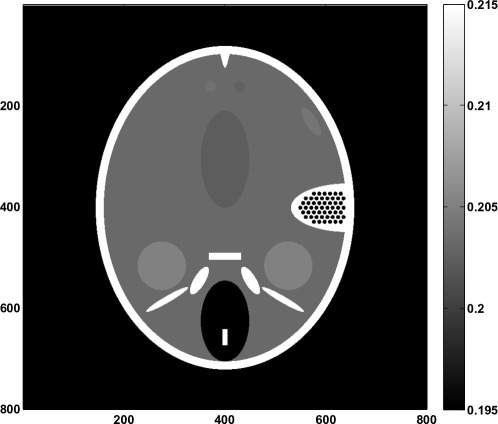

In the following numerical experiment we consider the problem of reconstructing an pixel image for = 100, 200, 400 and 800. We simulate parallel beam data acquired at equally spaced views over 180∘, with = 180, 360, 720 and 1440, respectively. Forward projection (multiplication by ) is implemented using the radon command in Matlab, while backward projection (multiplication by ) uses iradon with no filtering. Since depends on the object that we wish to reconstruct, we must consider a specific object to analyze the convergence of pSART. We use an slice of the FORBILD numerical head phantom YNDW12 , which consists of bone and soft tissue, and includes some low-contrast features. An image of the phantom for the case is shown in Fig. 7.